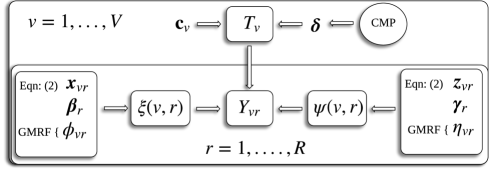

To aid with exposition, Figure 1 provides a graphical depiction of our proposed model. Let denote the collection of all model parameters except the inclusion indicators . Under the model determined by equations (1) - (5), the joint posterior density of the parameters, conditional on the observed data , is

With prior knowledge concerning the underlying structure of interest, it is possible to induce a prior on through a so-called conditional mean prior (CMP; Bedrick et al., 1996). Under this approach, we partition the -dimensional covariate space into regions and choose hypothetical covariate vectors so that is nonsingular. A prior is put on the mean response at these covariate values, , where applies componentwise. While the regression coefficients may be difficult to interpret, we can meaningfully assign a distribution to using a Beta distribution with shape parameters chosen to reflect the prior knowledge at the covariate values. Bedrick et al. (1996) show that if , then the induced prior is .